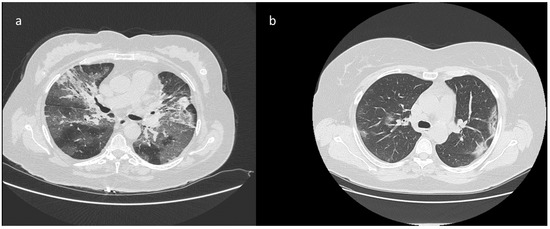

| CT Findings in 50 patients with discordance between RT-PCR and CT diagnosis after second CT reading | |||||

| Presence of GGOs with consolidation | 2 | 12 | >0.05 | ||

| Presence of GGOs without consolidation | 5 | 20 | |||

| Presence of consolidation without GGOs | 1 | 4 | |||

| High diagnostic confidence level | Bilateral multifocal GGO with predominantly peripheral distribution associated or not with septal thickening (crazy paving) and/or consolidations; multifocal GGO of rounded morphology associated or not with crazy paving and/or consolidations; multifocal GGO associated with findings of organizing pneumonia. |

| Intermediate diagnostic confidence level | GGO with diffuse distribution associated or not with crazy paving and/or consolidations; bilateral multifocal GGO and/or consolidations without a prevalent peripheral distribution and without rounded morphology; unilateral GGO with or without consolidation. |

| Low diagnostic confidence level | Isolated small areas of GGO and/or consolidations with non-rounded morphology were included in the low confidence level. |

| Negative for COVID-19 | Cases without the described alterations and with one or more of the following alterations were considered indicative of other diagnoses: isolated lobar or segmental consolidations, presence of solid or caveated nodules, presence of micro-nodules (centro-lobular micro-nodules and “tree in bud” pattern), smooth thickening of the interlobular septa with pleural effusion. |